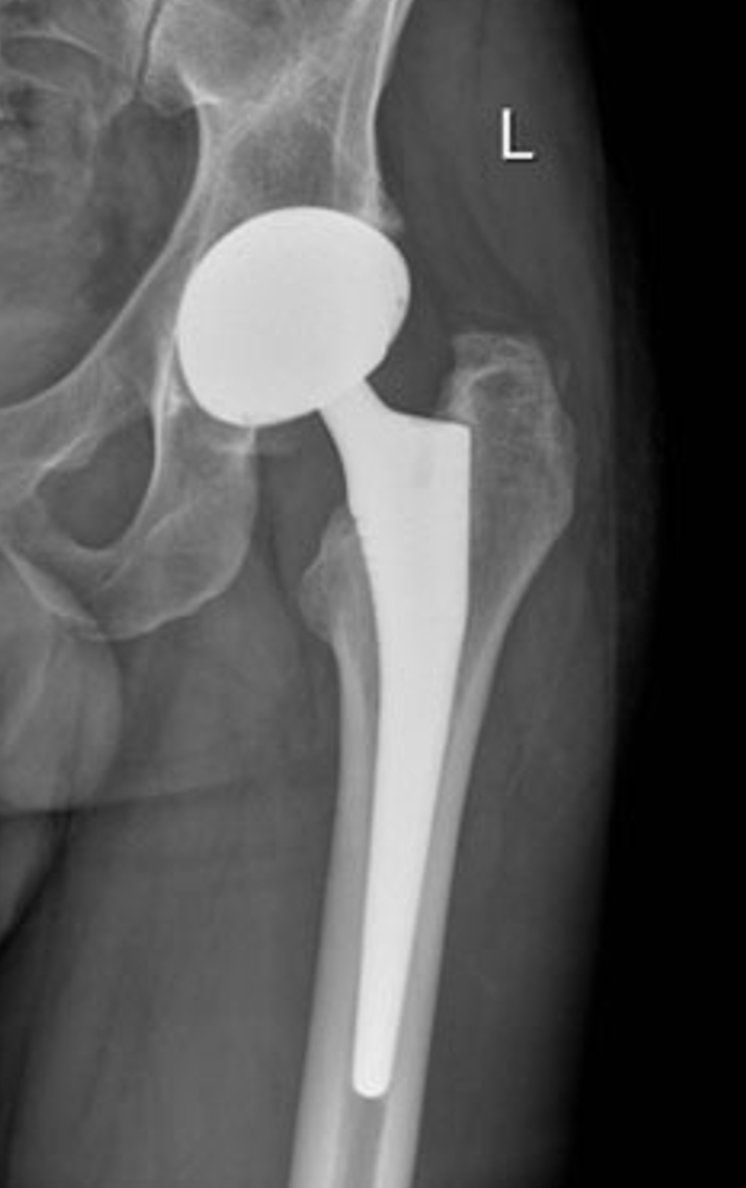

Pour les prothèses de hanche et de genou, nous préférons une hospitalisation courte afin d’optimiser les protocoles de récupération rapide et la surveillance du patient dans les 24-48h après l’opération.

Ainsi la durée d’hospitalisation pour une prothèse de hanche est de 1 à 2 jours et pour une prothèse de genou de 2 à 3 jours.